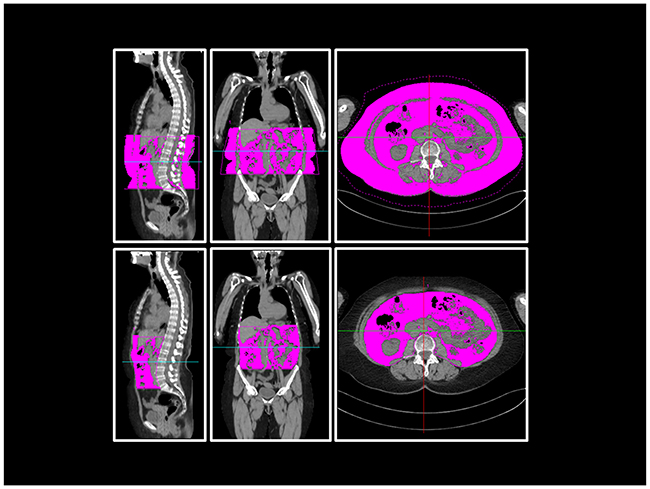

The visceral compartment is circumscribed by abdominal wall muscles. In the dorsal direction, the compartment was restricted by bony structures of the spine and, further caudal, by the pelvic structure. For the pelvic measurements, the intrapelvic part of the piriformis muscle and the psoas muscle cranial of its crossing with the inguinal ligament were included. Figure 6 illustrates these measurements by means of sample CT images.

Figure 6: Body fat composition measurement in WBLDCT. Example sagittal, coronal and axial views at the level of L3 of WBLDCT of a patient. Purple-coloured areas represent the measured total (above) and visceral (below) adipose tissue of the abdominal compartment.